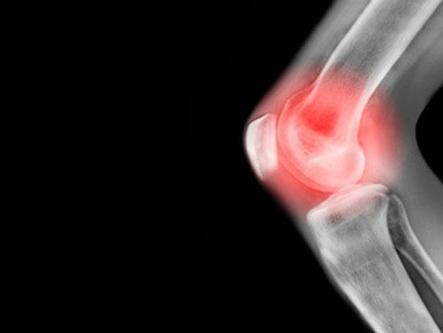

一說起關(guān)節(jié)痛,大家最先想到去哪個(gè)科室就診?風(fēng)濕科?骨科?反正不會(huì)想到和甲狀腺有什么關(guān)系。但是,在風(fēng)濕科門診,但凡遇到有關(guān)節(jié)痛、肌肉痛、肌無力的病人,醫(yī)生都會(huì)建議進(jìn)行甲狀腺檢查。因?yàn)椴还苁羌卓海醇谞钕俟δ芸哼M(jìn)癥)還是甲減(即甲狀腺功能減退癥),都有可能出現(xiàn)一些關(guān)節(jié)、肌肉的癥狀。

約30%—80%的甲減患者會(huì)出現(xiàn)肌肉和關(guān)節(jié)骨骼的癥狀,如關(guān)節(jié)酸痛、肌肉疼痛、僵硬、無力等。隨著甲減的控制,這些癥狀也會(huì)逐漸好轉(zhuǎn)。